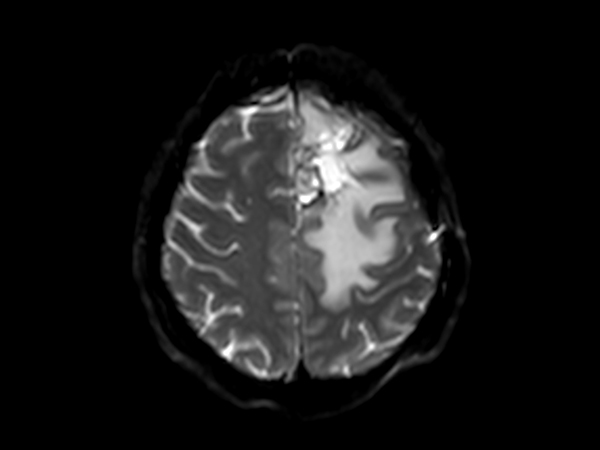

SmartSpeed Precise imaging for brain with glioblastoma

Kyushu University Hospital Japan